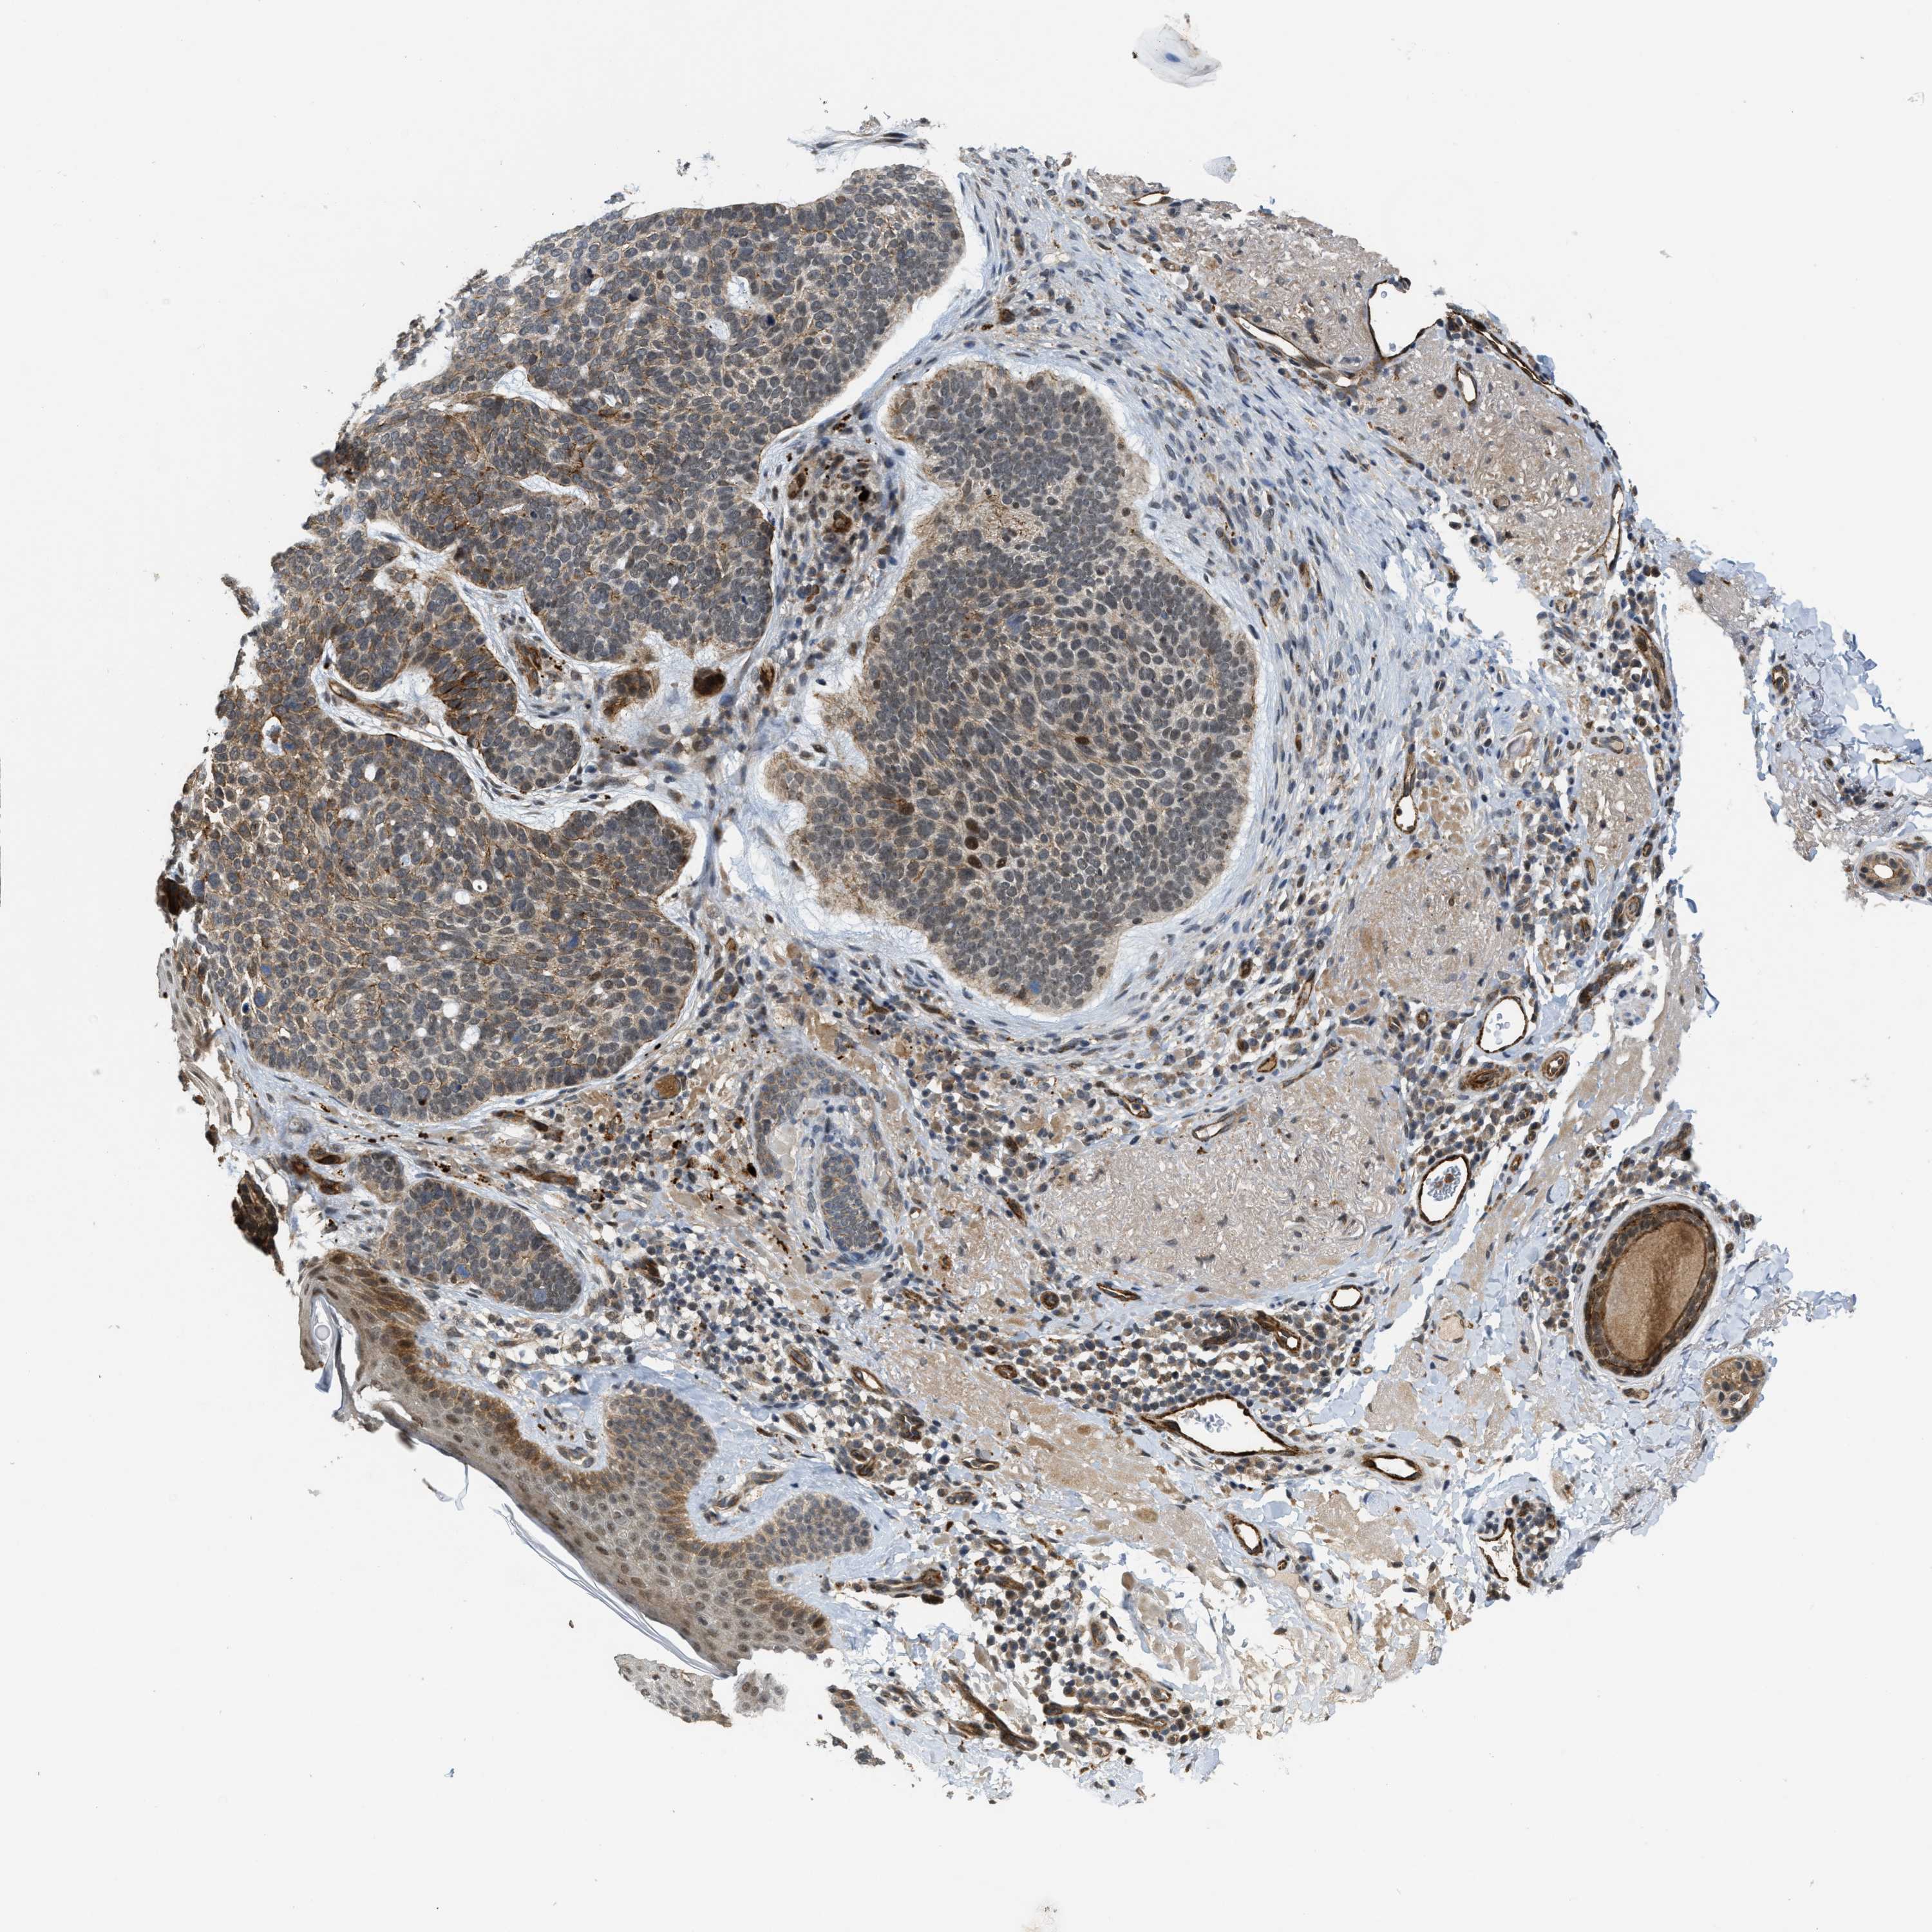

Basal cell and squamous cell cancer

SKIN CANCER - Protein expressioni

A mouse-over function shows sample information and annotation data. Click on an image to view it in a full screen mode. Samples can be filtered based on level of antibody staining by selecting one or several of the following categories: high, medium, low and not detected. The assay and annotation is described here.

Each image is clickable and will lead to virtual microscopy that enables deeper exploration of all samples and also displays staining intensity scores, fraction scores and subcellular localization as well as patient and tissue information for each sample.

Antibody HPA020880

Staining

Medium

Intensity

Moderate

Quantity

75%-25%

Location

Cytoplasmic/membranous,nuclear

Squamous cell carcinoma, NOS